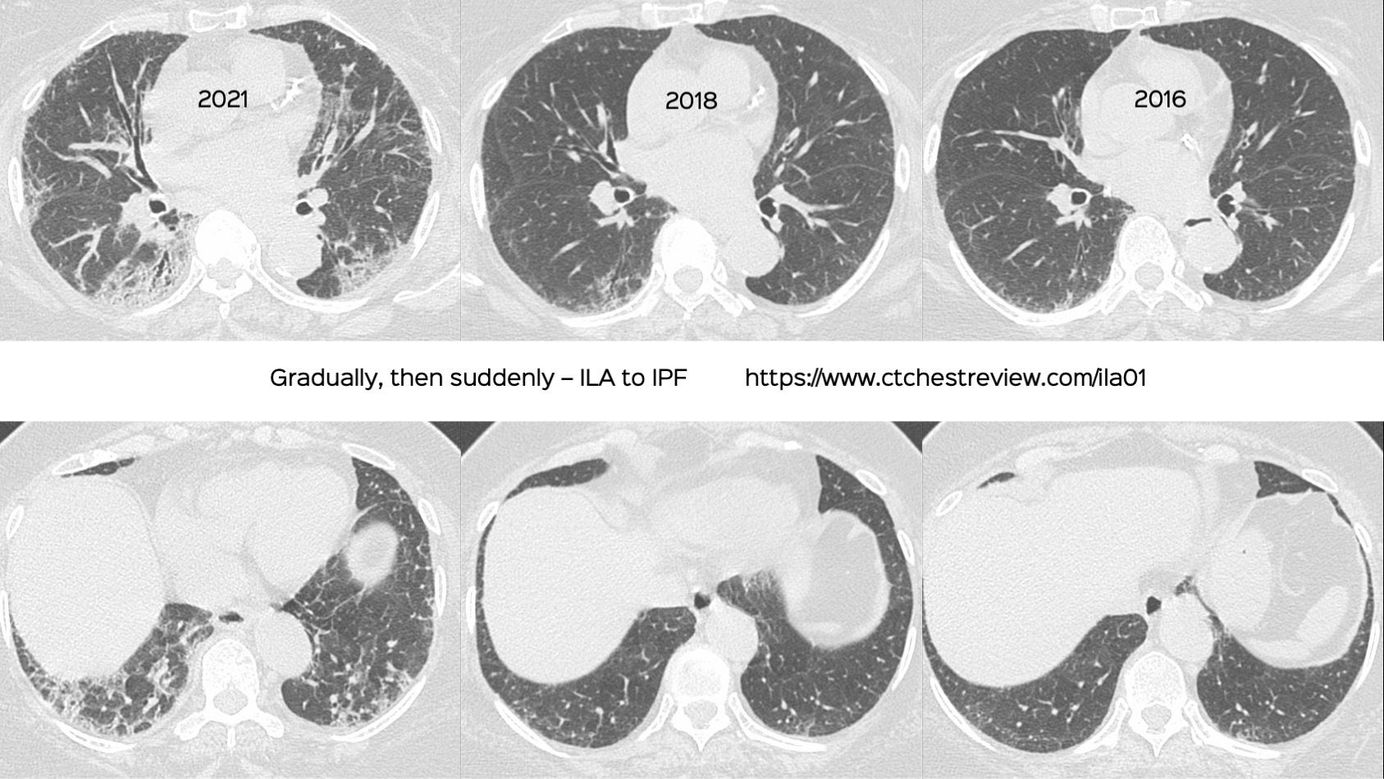

Case 36: Gradually, then Suddenly. ILA to ILD Members Public

Gradually, then suddenly. ILA to ILD